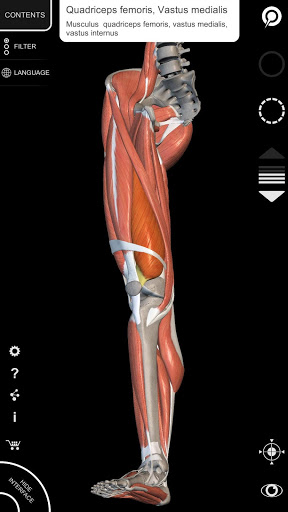

يتيح لك "Anatomy 3D Atlas" دراسة التشريح البشري بطريقة سهلة وتفاعلية.

من خلال واجهة بسيطة وبديهية، من الممكن ملاحظة كل بنية تشريحية من أي زاوية.

تتميز النماذج التشريحية ثلاثية الأبعاد بتفاصيل خاصة ودقة تصل إلى 4K.

يسهل التقسيم حسب المناطق والمناظر المحددة مسبقًا مراقبة ودراسة الأجزاء الفردية أو مجموعات الأنظمة والعلاقات بين الأعضاء المختلفة.

نماذج تشريحية ثلاثية الأبعاد

• الجهاز العضلي الهيكلي

• تصور العضلات من خلال مستويات الطبقات من الطبقات السطحية إلى الأعمق

• من خلال تحديد نموذج أو دبوس، يظهر المصطلح التشريحي ذي الصلة

• وصف العضلات: الأصل والإدخال والتعصيب والعمل